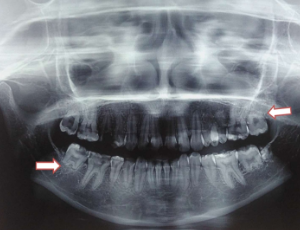

Radiation induced radicular hypoplasia: A rare case report

Irradiation is considered as one of the causes that may inhibit tooth development. Radiation exposure during the period of tooth development may result in impaired, delayed, or absolute failure to develop/eruption of the tooth. Radiation exposure at high dosage may also impair facial development in the pediatric population who had received radiation therapy for a malignant tumor in the head and neck region. Here we reported a case of Radiation-Induced Radicular Hypoplasia (RIRH) in a 19-year-old patient who received radiotherapy ten years ago for the Embryonal Rhabdo Myo Sarcoma of the soft palate.